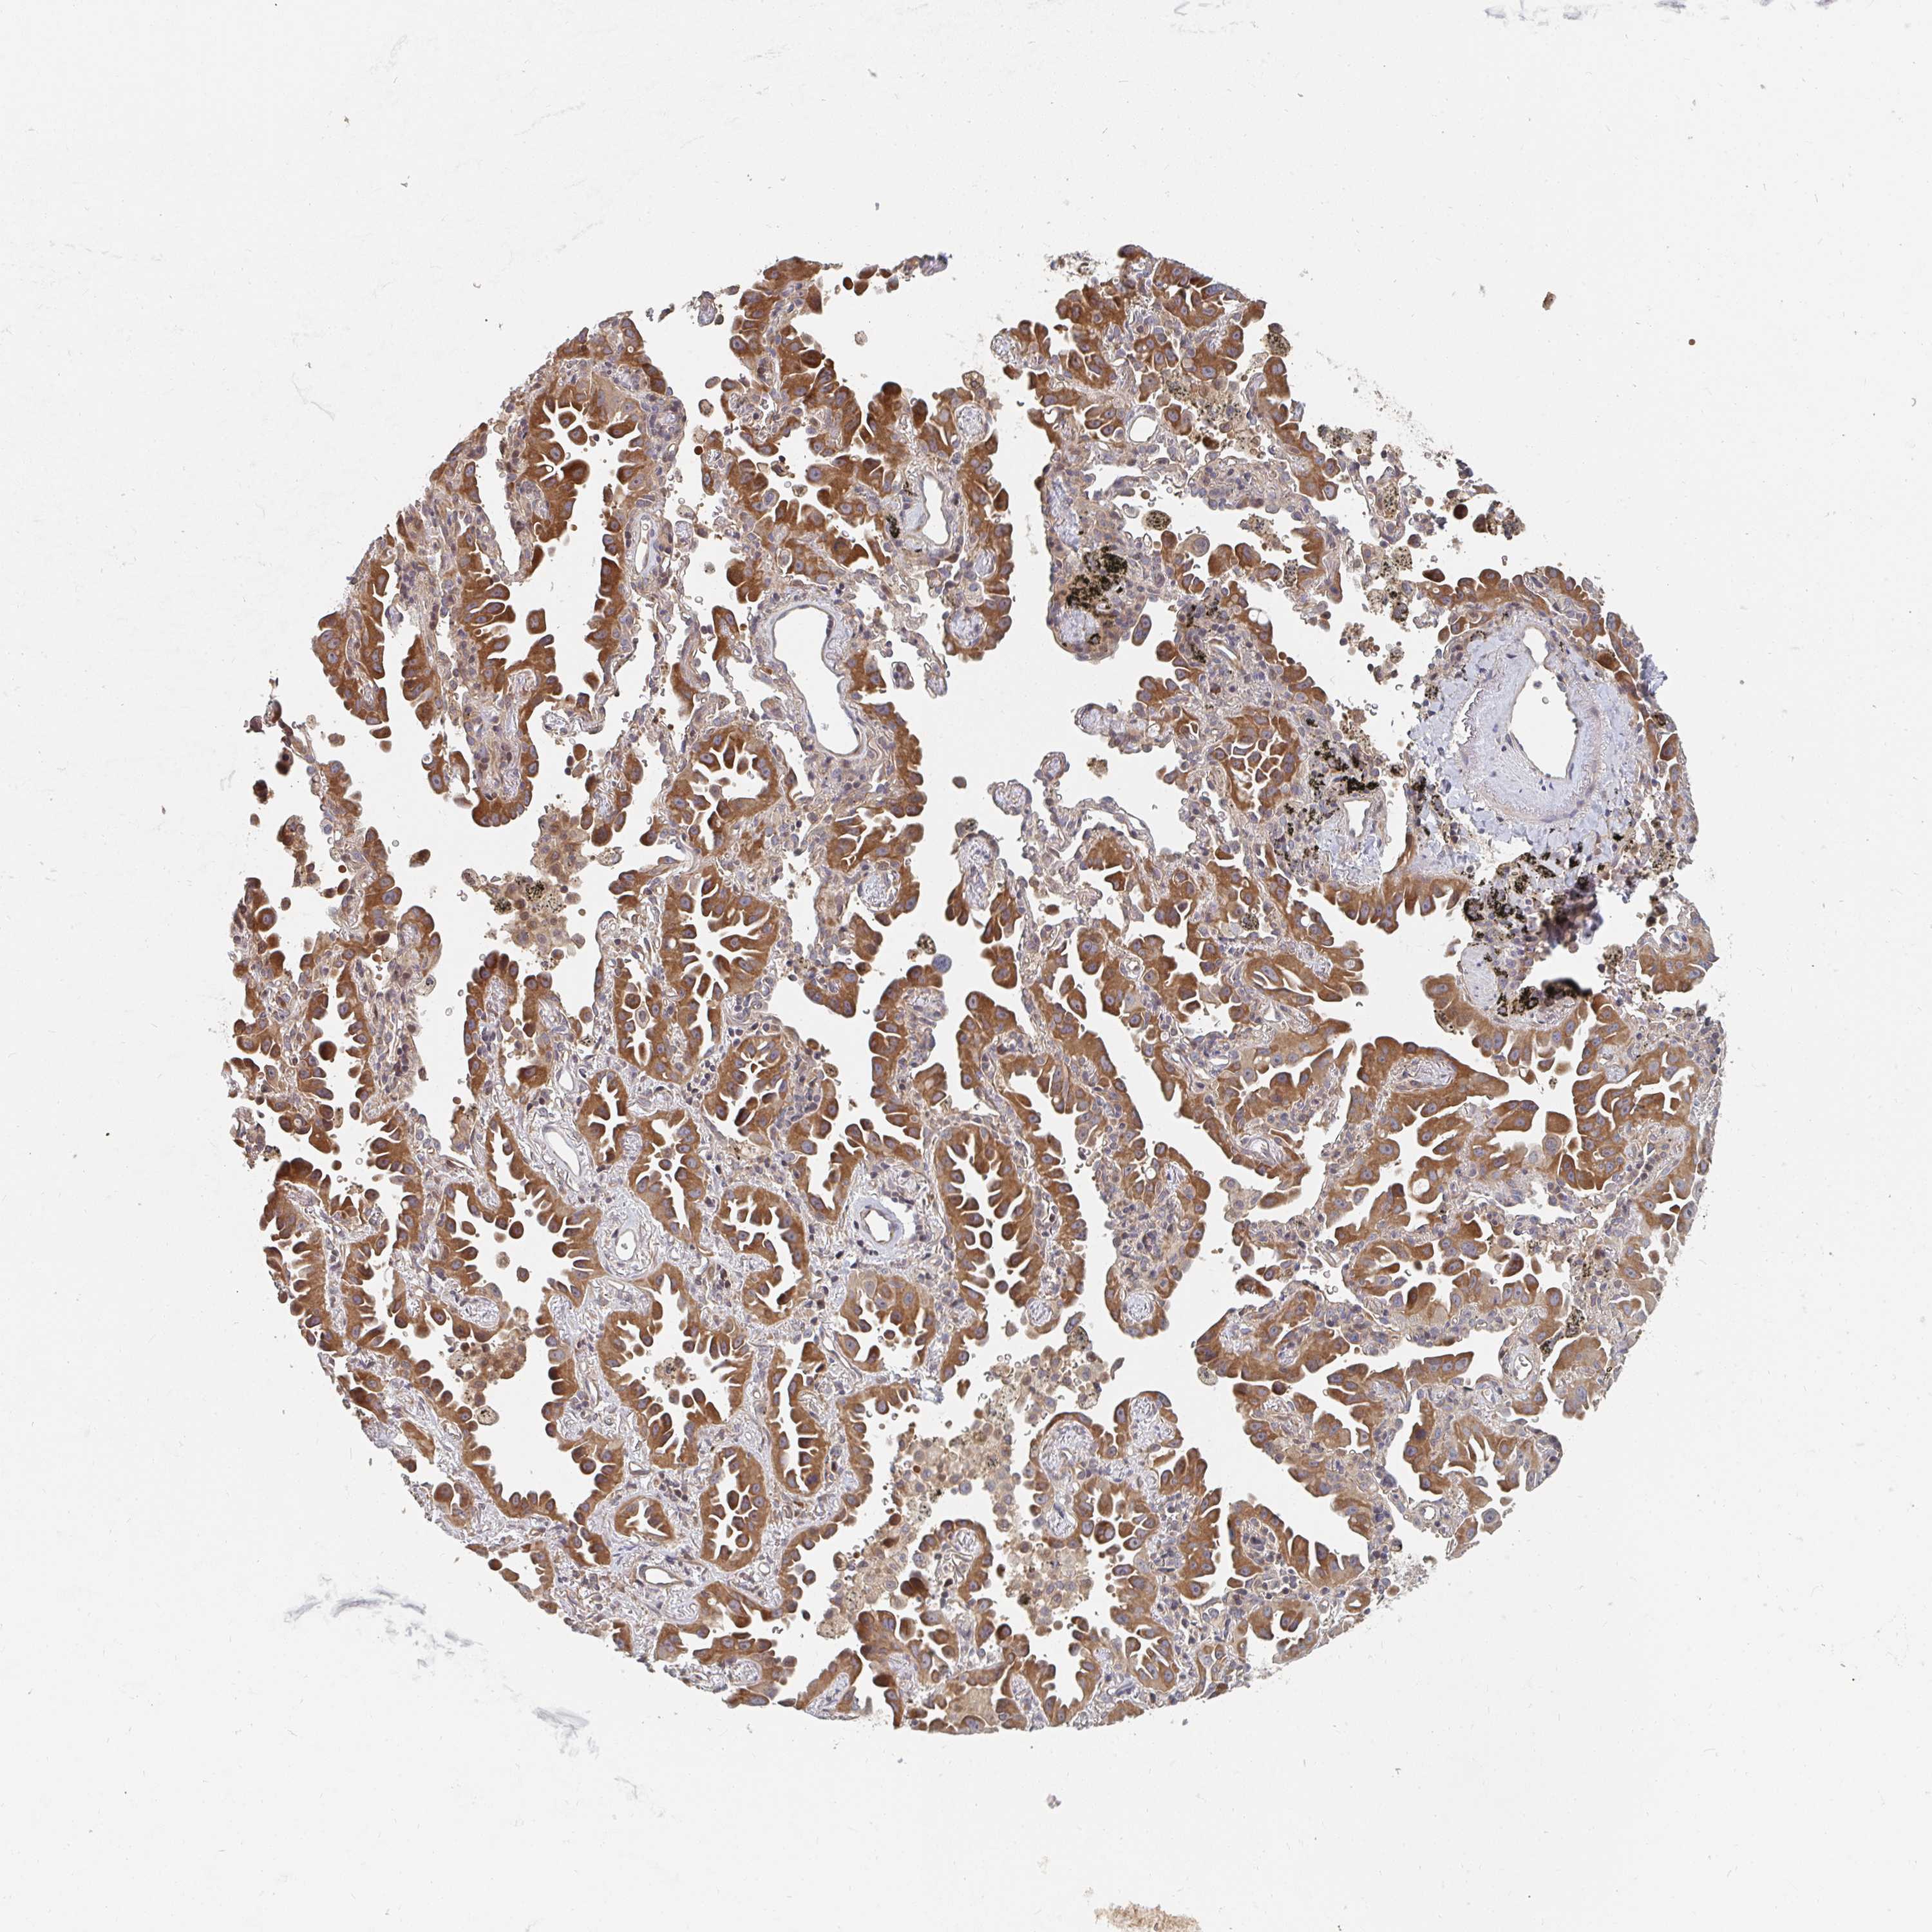

LUNG ADENOCARCINOMA (VALIDATION) - Interactive survival scatter ploti

The Survival Scatter plot shows the clinical status (i.e. dead or alive) for all individuals in the patient cohort, based on the same data that underlies the corresponding Kaplan-Meier plots. Patients that are alive at last time for follow-up are shown in blue and patients who have died during the study are shown in red.

The x-axis shows the expression levels (FPKM) of the investigated gene in the tumor tissue at the time of diagnosis. The y-axis shows the follow-up time after diagnosis (years). Both axes are complimented with kernel density curves demonstrating the data density over the axes. The top density plot shows the expression levels (FPKM) distribution among dead (red) and alive patients (blue). The right density plot shows the data density of the survived years of dead patients with high and low expression levels respectively, stratified using the cutoff indicated by the vertical dashed line through the Survival Scatter plot. This cutoff is automatically defined based on the FPKM cutoff that minimizes the p-score. The cutoff can be changed by dragging the vertical line or by entering a cutoff value in the square labeled "Current cut-off".

Under the Survival Scatter plot the p-score landscape (black curve; left axis) is shown together with dead median separation (red curve; right axis). Dead median separation is the difference in median mRNA expression between patients who have died with high and low expression, respectively. It is calculated as follows: median FPKM expression of dead patients with high expression - median FPKM expression of dead patients with low expression. This is intended to aid the user in visually exploring custom cutoffs and the associated p-scores and dead median separation.

Individual patient data is displayed and can be filtered by clicking on one or more of the category buttons on the top of the page. Categories describing expression level and patient information include: high, low, alive, dead, female, male and tumor stages. The scale of the x-axis can be toggled between linear and log-scale by clicking on the "x log" button. Mouse-over function shows TCGA ID, patient information and mRNA expression (FPKM) for each patient.

& Survival analysisi

Kaplan-Meier plots summarize results from analysis of correlation between mRNA expression level and patient survival. Patients were divided based on level of expression into one of the two groups "low" (under cut off) or "high" (over cut off). X-axis shows time for survival (years) and y-axis shows the probability of survival, where 1.0 corresponds to 100 percent.

PTEN is not prognostic in Lung Adenocarcinoma (validation)

Best expression cut offi

Based on the FPKM value of each gene, patients were classified into two groups and association between prognosis (survival) and gene expression (FPKM) was examined. The best expression cut-off refers the FPKM value that yields maximal difference with regard to survival between the two groups at the lowest log-rank P-value. Best expression cut-off was selected based on survival analysis .

When clicking on this number, the vertical dashed line indicating cut-off, the interactive survival plot, and the Kaplan-Meier curve will be adjusted to show results based on the best expression cut-off.

: 17.79

P scorei

Log-rank P value for Kaplan-Meier plot showing results from analysis of correlation between mRNA expression level and patient survival.

N/A

TCGA RNA samplesi

RNA-seq data is reported as average FPKM (number Fragments Per Kilobase of exon per Million reads), generated by the The Cancer Genome Atlas (TCGA) .

Normal distribution across the dataset is visualized with box plots, shown as median and 25th and 75th percentiles. Points are displayed as outliers if they are above or below 1.5 times the interquartile range. FPKM values of the individual samples are presented next to the box plot.

Average pTPM 20.7

Number of samples 105